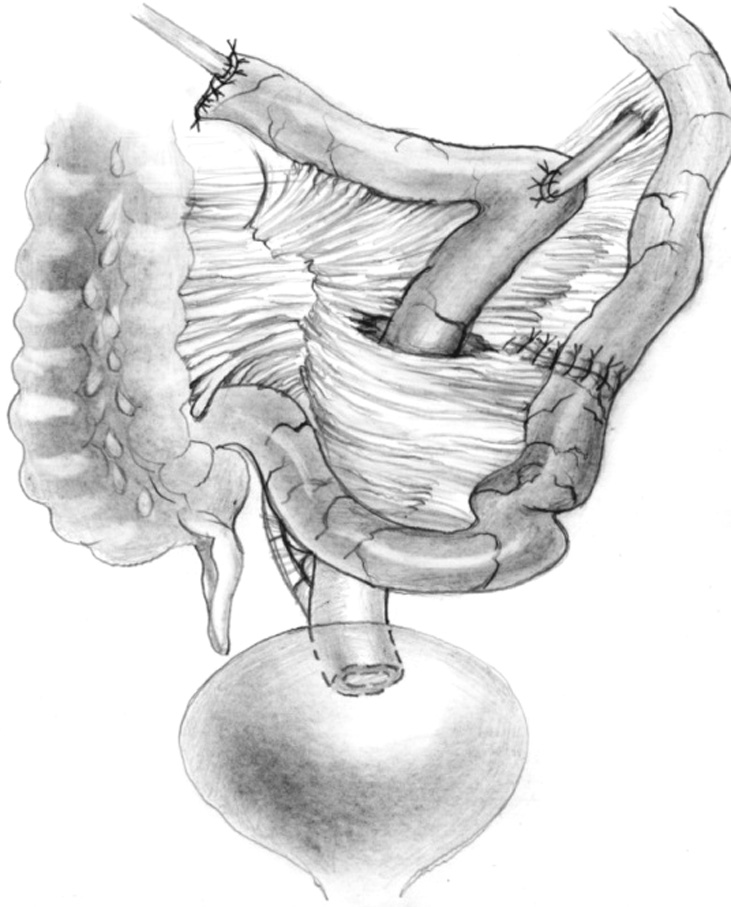

Bilateral small intestinal reconstruction of the ureters was performed in 40 (20.7%) patients. Most often, in 24 (60.0%) patients, U-shaped ileoureteroplasty was performed (Figs. 8 and 9), and more complex reconstructions were performed less often; that is, Y-shaped in 1 (2.5%) case, J-shaped in 3 (7.5%), L- and 7-shaped (Figs. 10 and 11) ileoureteroplasty in 6 (15.0%), and that with two separate ileografts in 6 (15.0%) cases.

Fig. 8. Bilateral U-shaped ileoureteroplasty

Bilateral ileoureteroplasty is a more complex and traumatic surgical procedure. Most often, the need for the procedure arises in case of radiation damage to the urinary tract. Partial or complete replacement of both ureters can be performed simultaneously or in stages using one or two separate segments of the bowel. The staged approach to surgery depends on the severity of the patient’s condition and destructive changes in the urinary tract. Bilateral ileoureteroplasty becomes more complicated because the length of the ureteral sections requiring replacement increases. This is due to (1) a wide and traumatic surgical approach; (2) the need to exclude a more extended segment from the small intestine; (3) the inclusion of a long convoluted segment(s) of the intestine into the urinary system, which leads to a larger area of resorption and an increased risk of metabolic disorders; and (4) the abovementioned complicated aspects of plastic surgery of the right ureter in the isoperistaltic position.